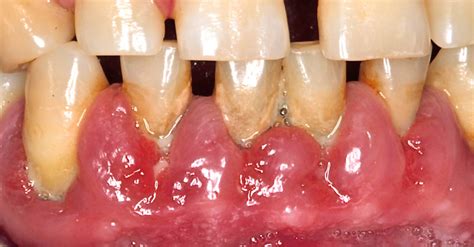

La hiperplasia gingival es un trastorno bucal que se caracteriza por un crecimiento excesivo del tejido gingival, es decir, de las encías. En los pacientes que padecen esta afección, las encías se inflaman y aumentan considerablemente de tamaño. En los casos graves, las encías pueden llegar a comenzar a cubrir los dientes. Es el aumento difuso y relativamente vascular, nodular o liso de las encías; con el paso del tiempo puede llegar a cubrir toda la dentadura.

Es importante destacar que la hiperplasia gingival no solo afecta la estética de la sonrisa, sino que también puede ocasionar molestias y complicaciones en la salud bucal. Algunos de los síntomas más comunes incluyen encías inflamadas, enrojecidas, sensibles y propensas a sangrar, así como la aparición de bolsas de tejido gingival excesivo alrededor de los dientes.

- Este aumento crónico del volumen de los tejidos gingivales, que usualmente comienza a nivel de las papilas gingivales interdentales anteriores, para extenderse a continuación al sector posterior de la boca, adquiriendo la encía un aspecto lobulado.

- Después de algunos años, en algunos pacientes, la encía puede aumentar de volumen hasta recubrir casi todas las piezas dentarias.

- Uno de los síntomas más evidentes de la hiperplasia gingival es el crecimiento excesivo del tejido de las encías.

- Las encías afectadas por la hiperplasia gingival suelen presentar enrojecimiento e inflamación.

- Otra señal común de la hiperplasia gingival es el sangrado de las encías.